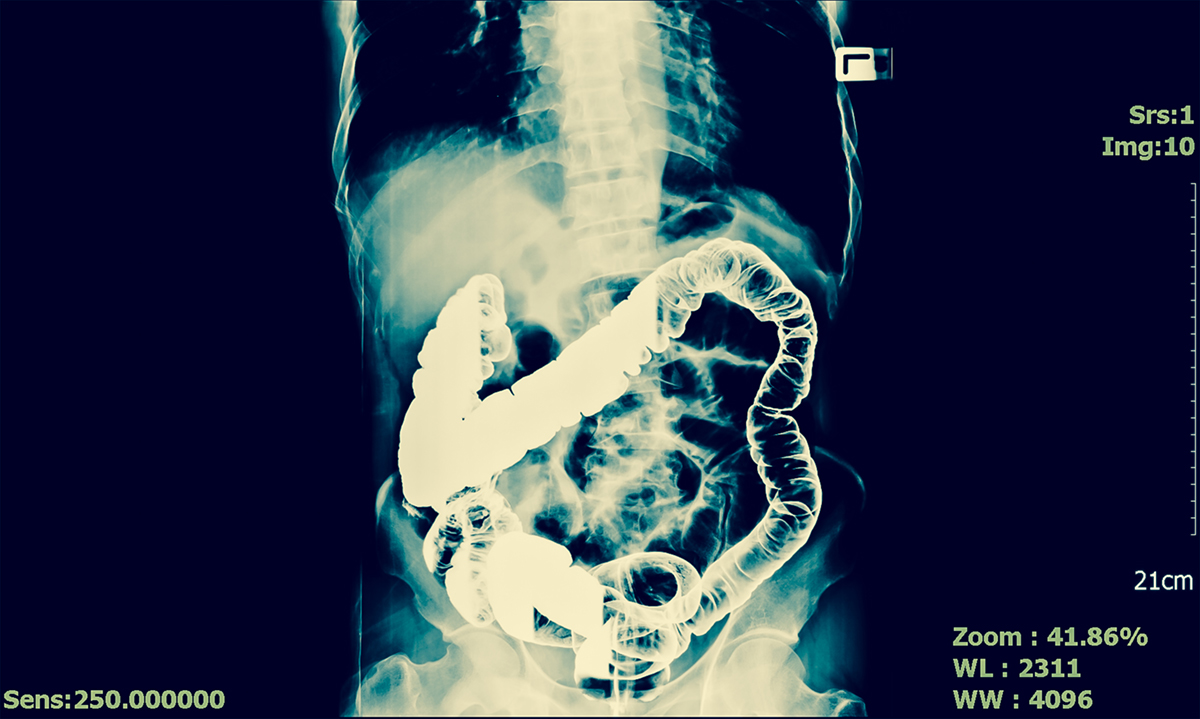

X-ray of abdomen with contrast